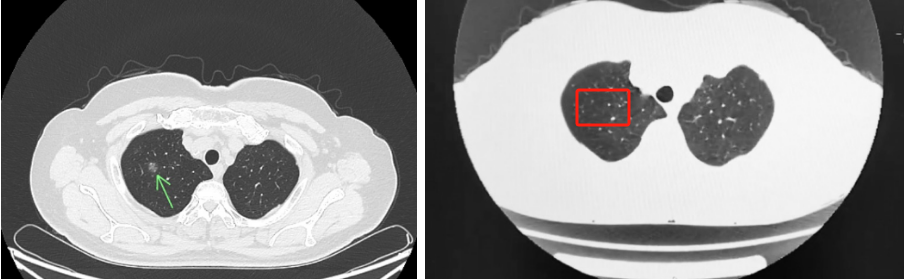

近日,湖北省第三人民医院(湖北省中山医院)中医科成功运用中医药疗法,帮助一位1.1厘米的肺结节患者李奶奶避免了手术治疗。复查CT时,放射科医生也惊喜表示:“一个月前还清晰可见的1.1厘米结节,现在几乎消失!”71岁的李奶奶手持显示结节仅余2-3毫米的报告单,喜悦之情溢于言表。此前,她因外院建议手术而深陷焦虑,最终选择中医治疗。

中药复方通过多靶点调控,有效逆转局部炎性微环境,促进异常增生组织的消散与吸收,一段时间后,李奶奶结节的明显缩小。目前,李奶奶仍在门诊随访调治,结节稳定未见反复,困扰多年的咽部异物感、睡眠质量也得到改善。她感慨道:“没想到几副汤药,竟能化解开胸之忧!”